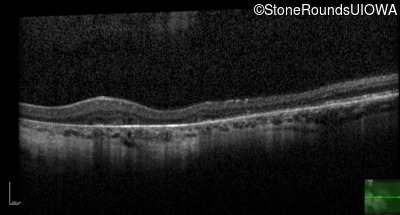

Optical Coherence Tomography - Left - 20/30 +1 sc

Exemplar / OCT Stack